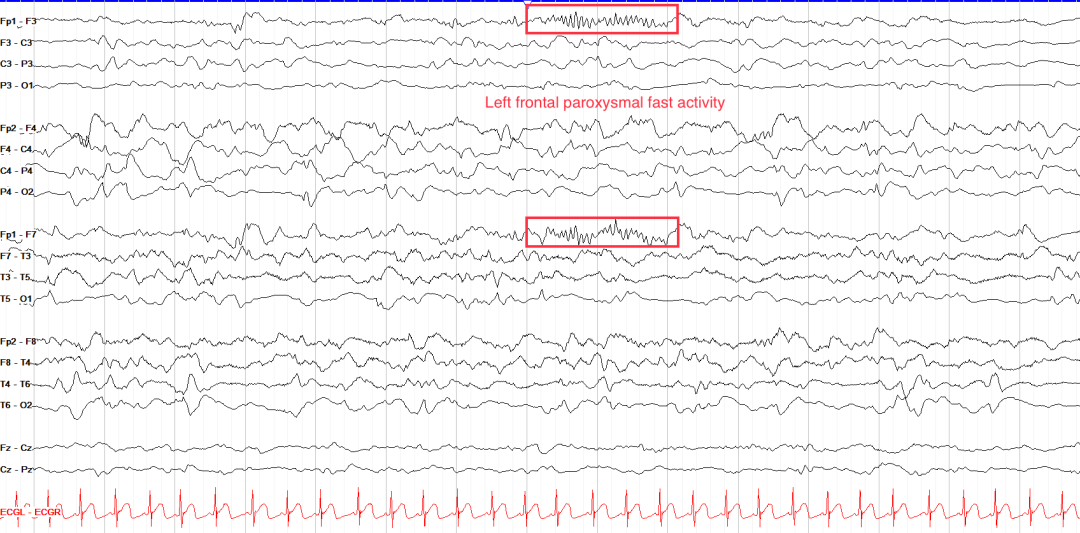

2.额叶癫痫(Frontal Lobe Epilepsy, FLE)

波形特征:

局灶性快活动:13-30 Hz低幅节律,常伴肌电伪迹(图3B)。

继发双侧同步放电(SBS):局灶棘波迅速扩散为双侧同步化放电。

临床关联:夜间丛集性发作,伴过度运动或不对称强直姿势。

3.阵发性快活动(Paroxysmal Fast Activity)

时域特征:

突发性β/γ频段(20-50Hz)节律,持续1-10秒,局灶或泛化分布

振幅渐增(Build-up)或渐减(Decay),常伴肌电伪差

阵发性快活动

临床关联:

局灶性:额叶癫痫(如扣带回起源)、局灶皮质发育不良(FCDⅡb型)